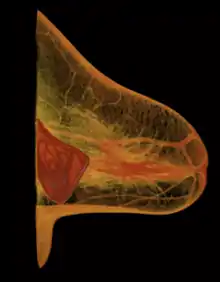

- Subglandular: the breast implant is emplaced to the retromammary space, between the breast tissue (the mammary gland) and the pectoralis major muscle (major muscle of the chest), which most approximates the plane of normal breast tissue, and affords the most aesthetic results. Yet, in women with thin pectoral soft-tissue, the subglandular position is likelier to show the ripples and wrinkles of the underlying implant. Moreover, the capsular contracture incidence rate is slightly greater with subglandular implantation.

- Subfascial: the breast implant is emplaced beneath the fascia of the pectoralis major muscle; the subfascial position is a variant of the subglandular position for the breast implant.[90] The technical advantages of the subfascial implant-pocket technique are debated; proponent surgeons report that the layer of fascial tissue provides greater implant coverage and better sustains its position.[91]

- Subpectoral (dual plane): the breast implant is emplaced beneath the pectoralis major muscle, after the surgeon releases the inferior muscular attachments, with or without partial dissection of the subglandular plane. Resultantly, the upper pole of the implant is partially beneath the pectoralis major muscle, while the lower pole of the implant is in the subglandular plane. This implantation technique achieves maximal coverage of the upper pole of the implant, whilst allowing the expansion of the implant's lower pole; however, "animation deformity", the movement of the implants in the subpectoral plane can be excessive for some patients.[92]

- Submuscular: the breast implant is emplaced beneath the pectoralis major muscle, without releasing the inferior origin of the muscle proper. Total muscular coverage of the implant can be achieved by releasing the lateral muscles of the chest wall—either the serratus muscle or the pectoralis minor muscle, or both—and suturing it, or them, to the pectoralis major muscle. In breast reconstruction surgery, the submuscular implantation approach effects maximal coverage of the breast implants. This technique is rarely used in cosmetic surgery due to high risk of animation deformities.

- Prepectoral or subcutaneous: in a breast reconstruction following a skin-sparing or skin- and nipple-sparing mastectomy, the implant is placed above the pectoralis major muscle without dissecting it so that the implant fills directly the volume of the mammary gland that has been removed. To avoid the issue of capsular contracture, the implant is often covered frontally or completely with a mesh in biomaterial, either biological or synthetic.